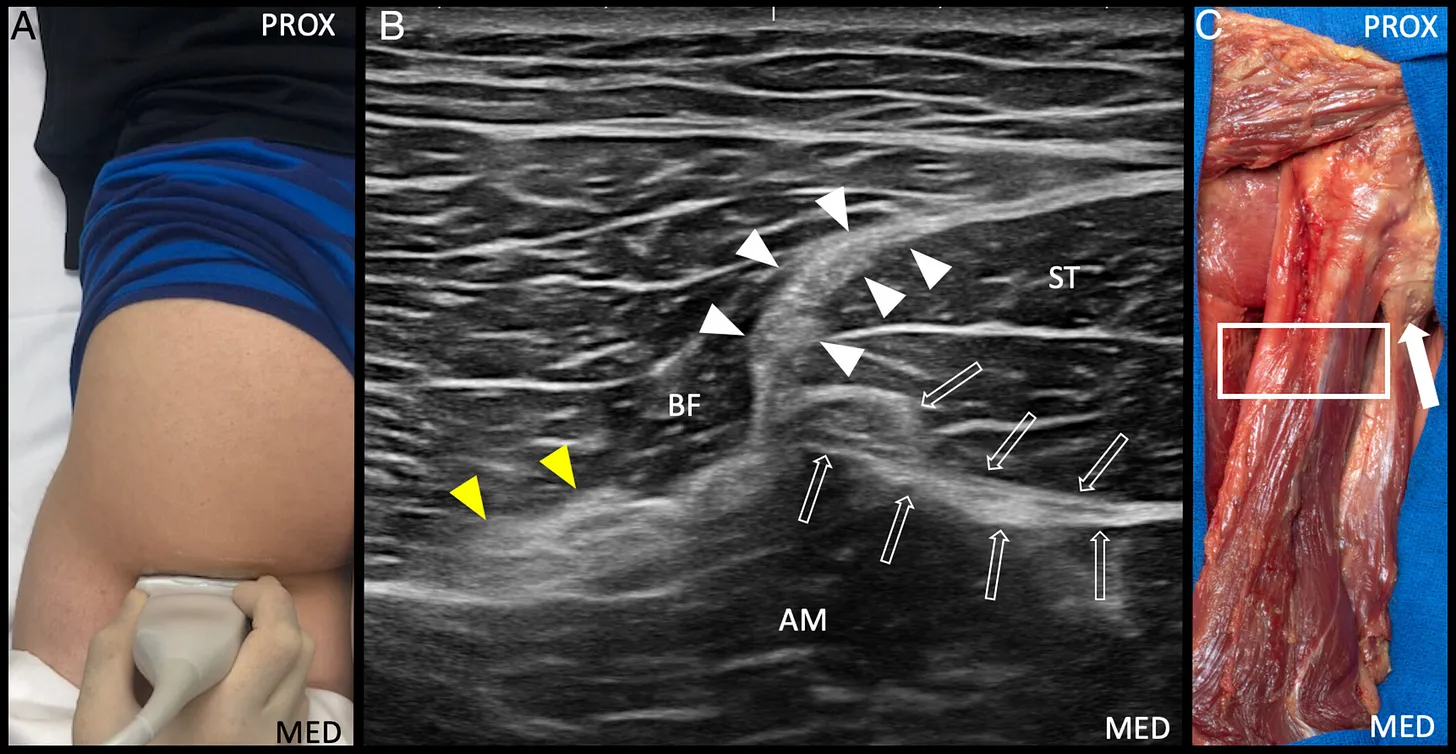

A. Posición anatómica axial del transductor ecográfico para obtener la imagen del “triángulo hiperecogénico” formado por el tendón conjunto, el tendón del semimembranoso y el nervio ciático.

B. Imagen ecográfica en corte transversal del “triángulo hiperecogénico”.

C. Preparación cadavérica que muestra la posición del transductor para la visualización del “triángulo hiperecogénico”.

AM: músculo aductor mayor; BF: músculo bíceps femoral; ST: músculo semitendinoso;

MED: medial; PROX: proximal;

puntas de flecha blancas: tendón conjunto;

flecha abierta: tendón del semimembranoso;

flecha cerrada: tendón de origen isquiocondíleo del aductor mayor;

puntas de flecha amarillas: nervio ciático;

rectángulo: posición del transductor.